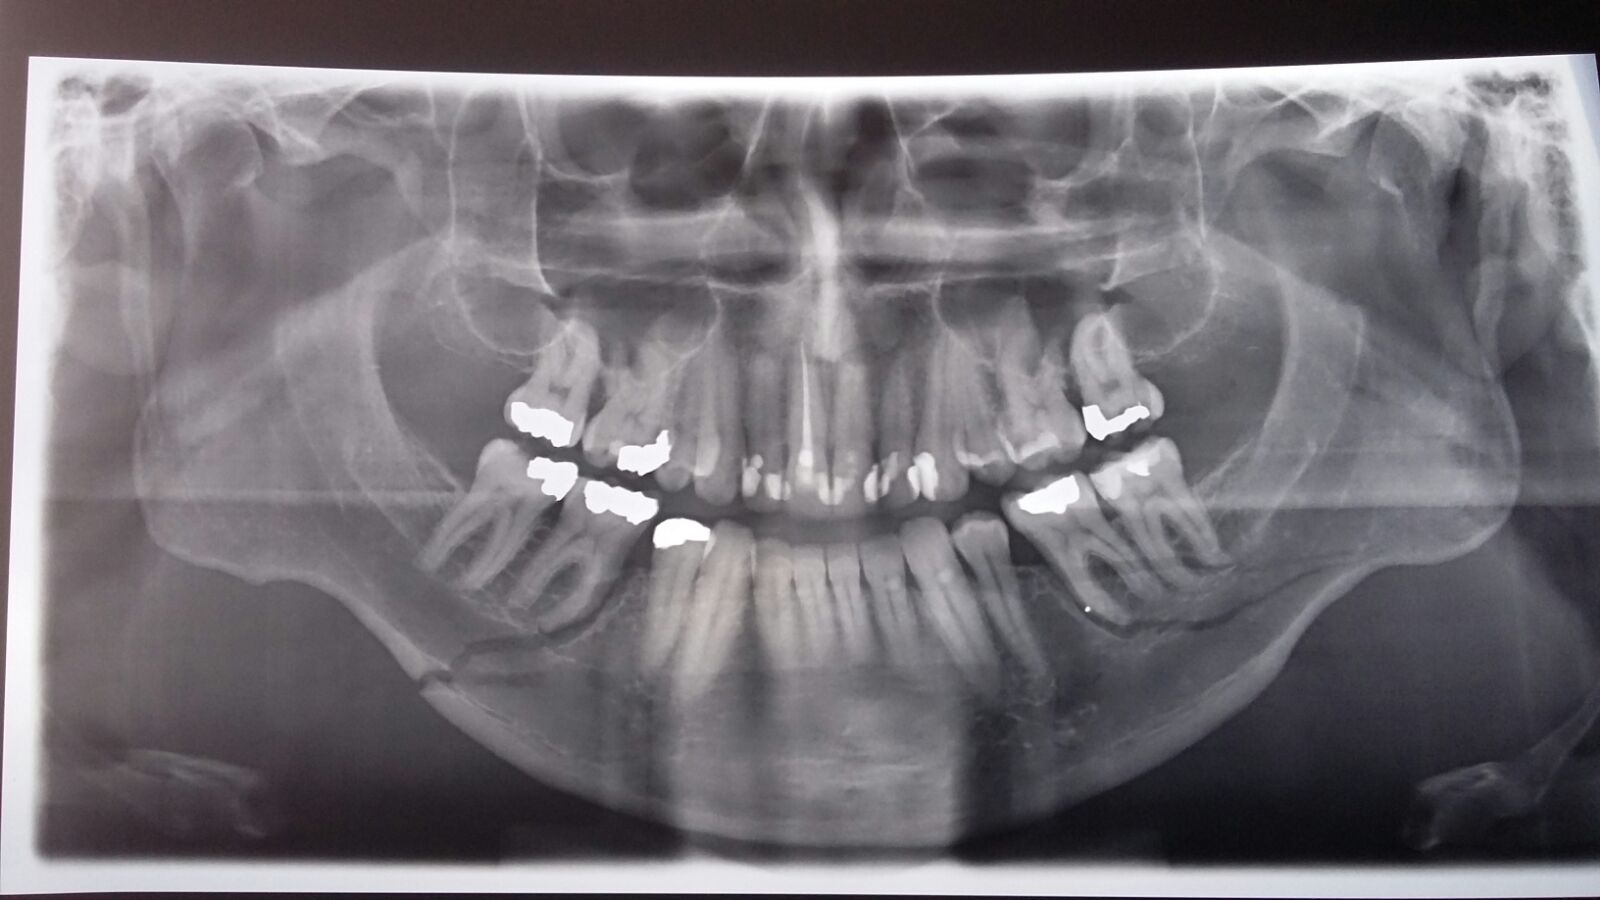

In eind november 2015 heb ik mijn kaak op 2 plekken gebroken (helemaal doorgebroken) en beschadigde kaakgewrichten (en een schedelfractuur)

Nu ben ik hiervoor geopereerd, heb 2 plaatjes op de kaak gekregen die blijvend zijn, en voor 6 weken had ik ook een metalen draden om mijn kiezen heen gekregen.

Die zijn in januari weer verwijderd.